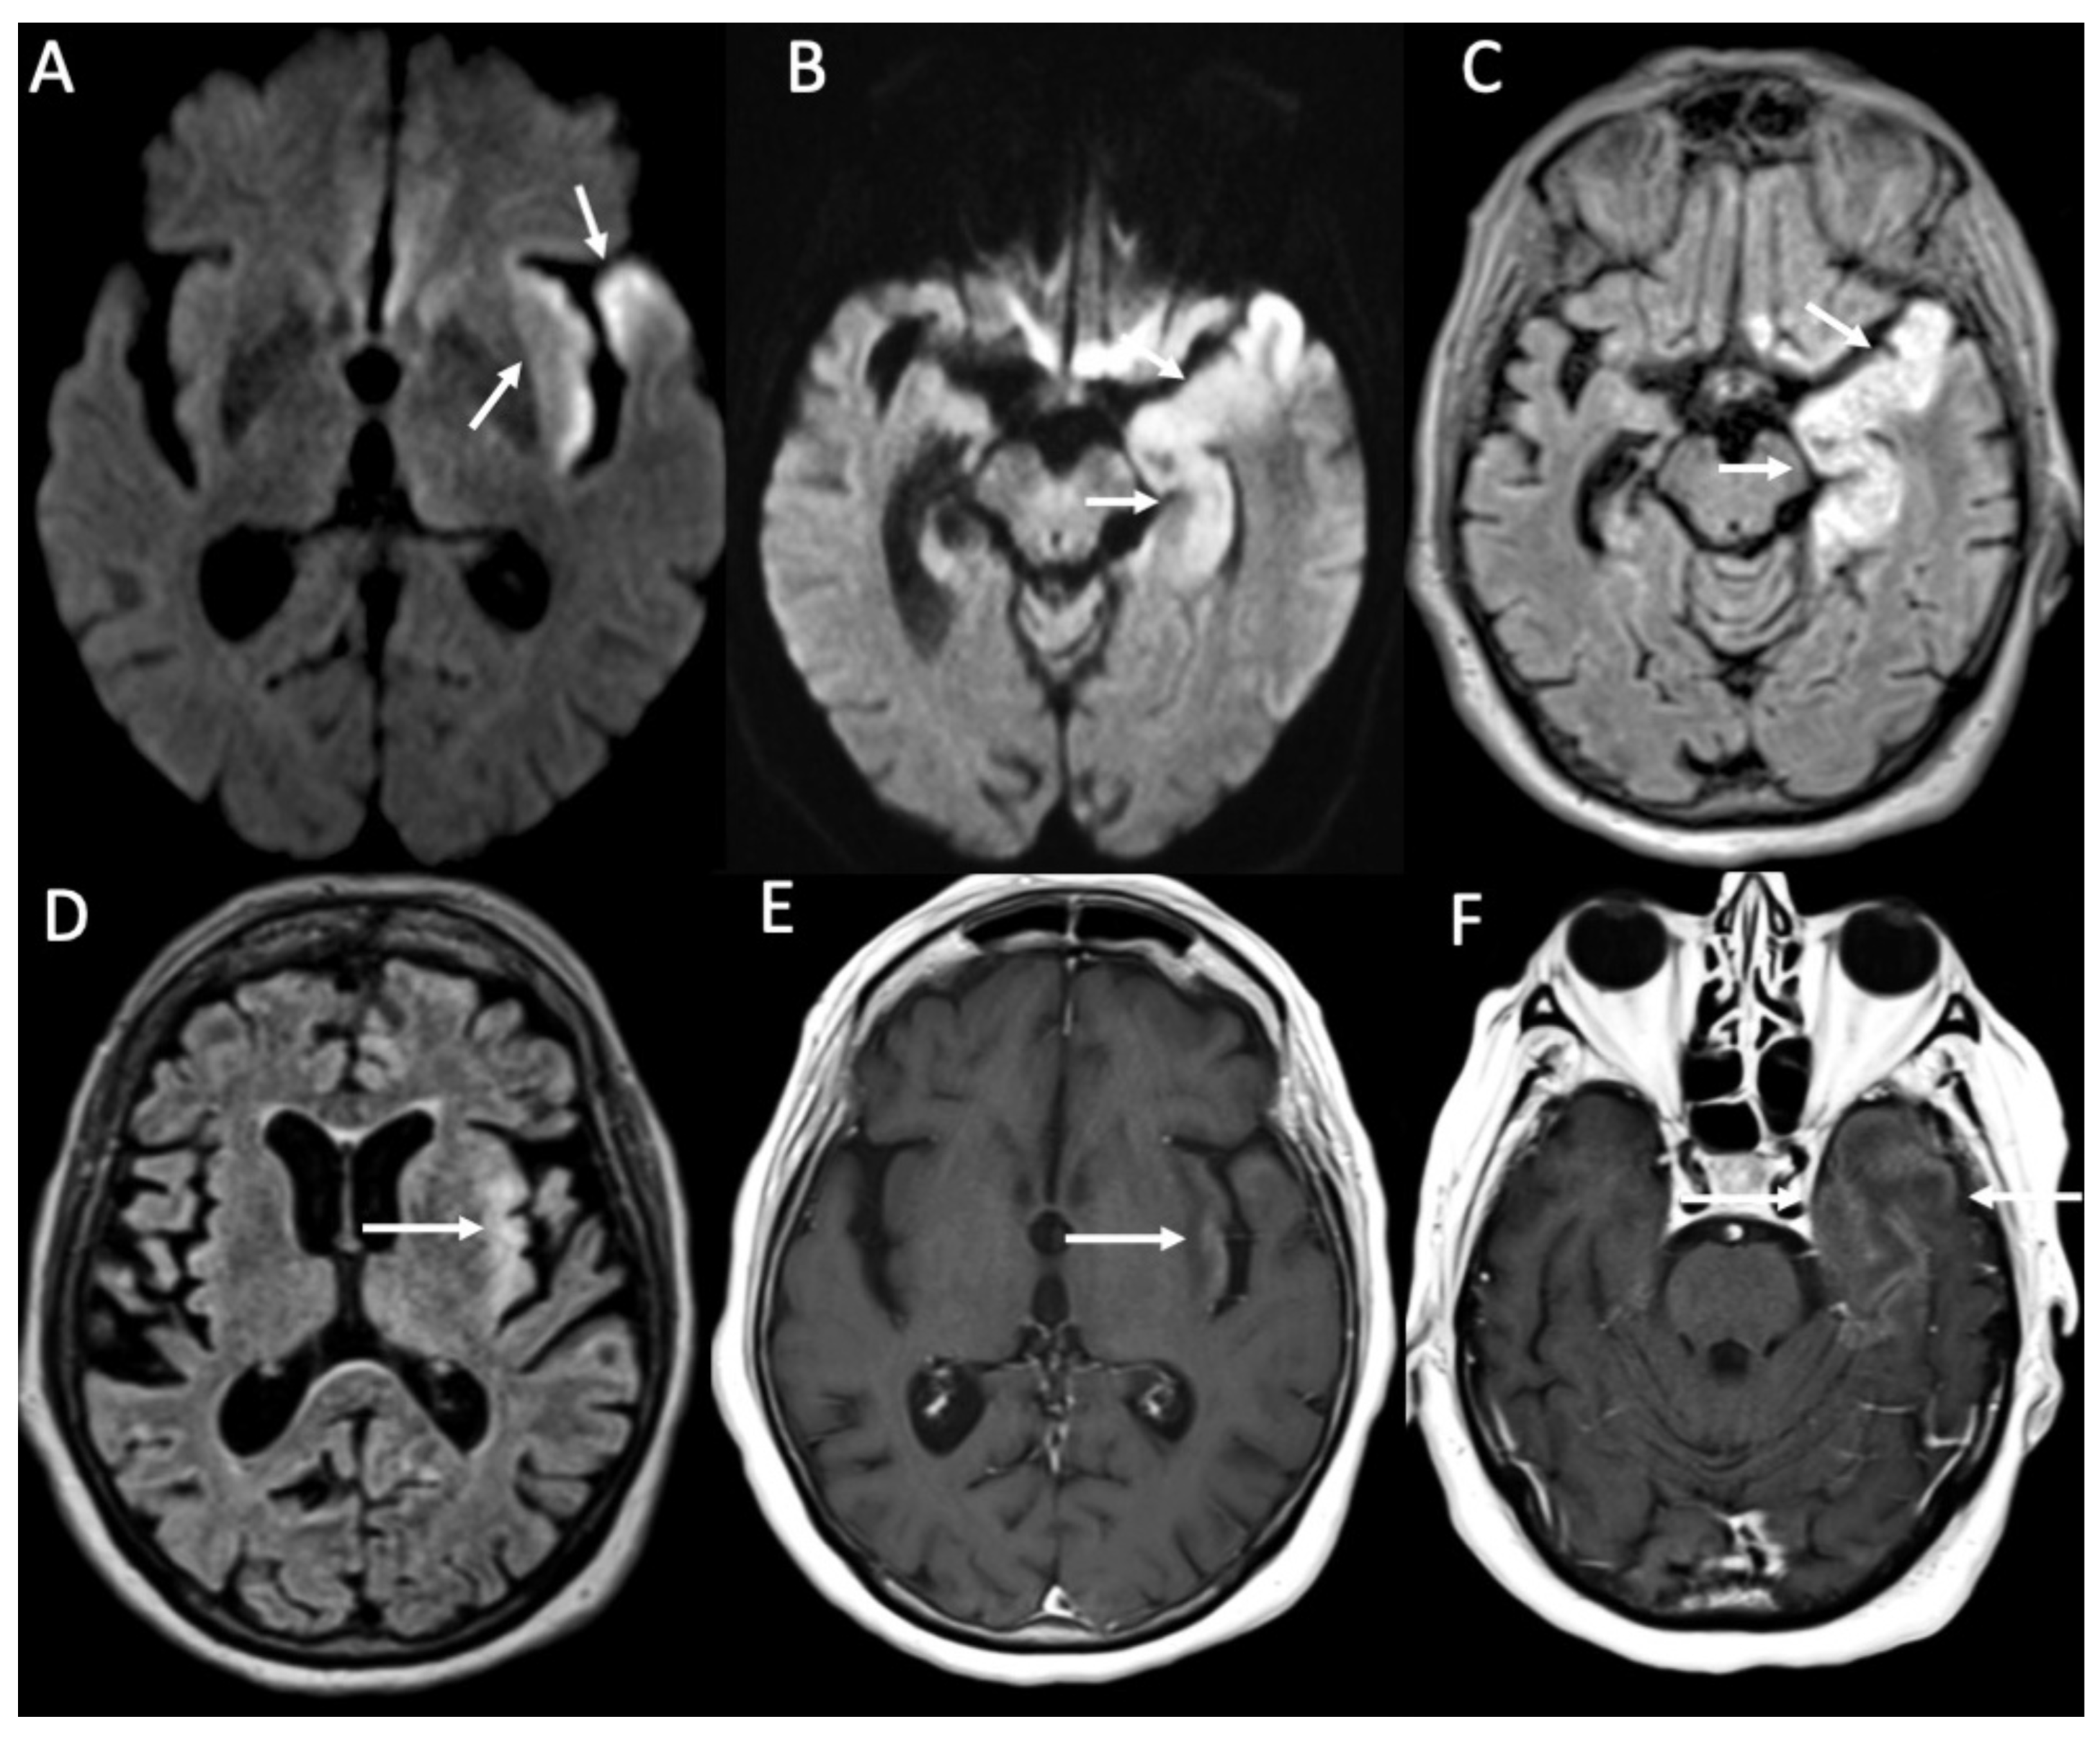

| Cryptococcus Neoformans | • Leptomeningeal enhancement • Cryptococcoma • Gelatinous pseudocysts |

| Candida albicans | • Microabscesses • Vascular lesions |

| Aspergillus fumigatus | • Abscesses • Vascular lesions |

4. Fungal Meningitis